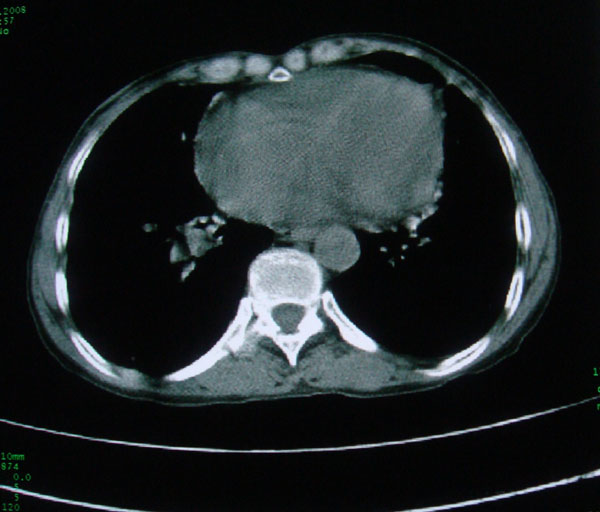

标题: CT15046:F59Y,咳嗽间断咳血丝痰就诊. [打印本页]

咳嗽\间断咳血丝痰就诊.

考虑支气管扩张并感染

1慢支伴感染;右下肺周围型肺癌。

本例应该是“慢性疾病并发多种合并症”即:慢支并感染并支气管扩张征!结合病灶分布 形态分析,不除外合并“继发性肺结核”!

慢性支气管炎伴全小型肺气肿、支气管扩张、感染、间质纤维化。